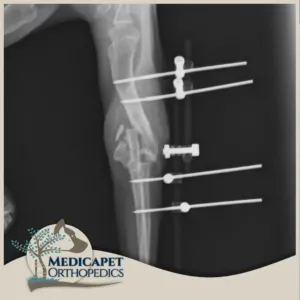

Eksternal Fiksatörler

Bazı kırıklarda kemiğe içeriden müdahale etmek uygun olmayabilir. Bu sebeple kırığı dışarıdan ya da çok küçük bir kesinin içinden redükte ettikten sonra vücudun dış kısmına yerleştirdiğimiz sabitleyici mekanizmalar ile sabit tutmayı amaçlayan ameliyatlar yaparız. Eksternal fiksatör kullanımı kesinlikle iyi bir biyomekanik araştırması ve tecrübesi gerektirir. Çünkü hastamız kırık uzvunu kullanmaya başladığında oluşacak gerilim ve yük bu fiksatörler üzerine binecektir. Bu sebeple yerleştirilecek olan fiksatörün konumu, yönü ve kemiğe göre pozisyonu büyük önem taşır. Biz klinik eksternal fiksatör uygulamalarımızda genellikle İlizarov sirküler monoblok ve her iki tekniğin kombine şekilde uygulandığı teknikleri başarıyla kullanıyoruz. Eksternal fiksatörler en çok, çok parçalı kırıklarda kullanılmaktadır. Bazı parçalı kırıklar içeriden müdahale edilirse eskisinden daha kötü hale gelebilirler. Bu sebeple kas doku bütünlüğünü bozmadan, mevcut kasların kırılan kemiğe desteğini sağlamak için insizyonsuz ya da minimal invaziv girişimlerde bulunuyoruz.